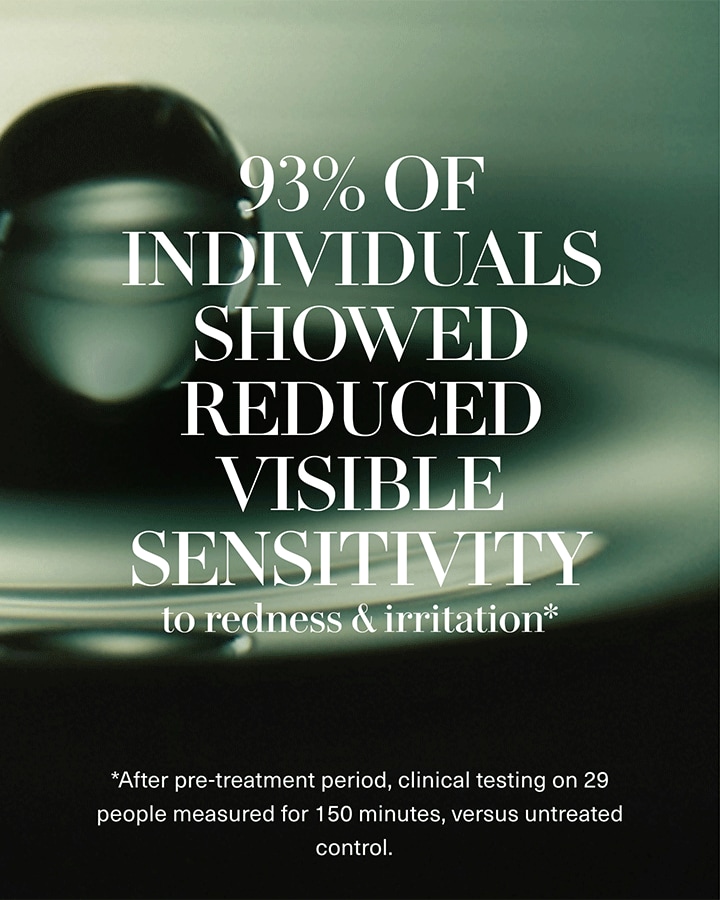

Lightweight yet deeply replenishing, this powerful hydrator transforms skin with sea-sourced energy for your most radiant, healthy-looking, fresh complexion yet. This high-speed serum creates a micro-cloud of moisture, maintaining a haven of healthy hydration where skin can thrive.

- Visibly revitalized, glowing skin